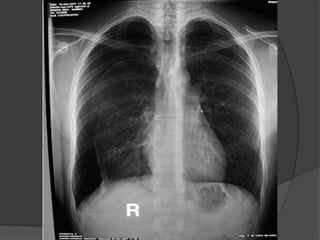

-En radiografía de tórax es muy visible una

línea muy fina que limita la zona con

estructura pulmonar y la separa del

neumotórax.

-Signos radiológicos como en neumotórax

pequeño.